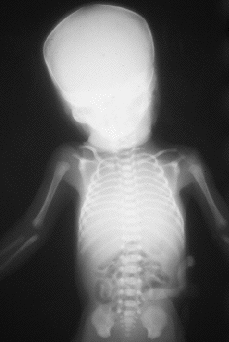

Se practica una radiografía postmortem que informa de la presencia de aire intestinal y pulmonar en las grandes vías aéreas, y de la ausencia de hemivértebras.

El informe autópsico es el siguiente: Feto hembra de treinta semanas de gestación, según peso y longitudes occipito-sacra y del pie, que presenta inmadurez visceral grado II, polimalformado, presentando anomalías faciales, hipoplasia pulmonar (índice peso corporal/peso pulmonar = 0,007), surco simiesco bilateral, bazo supernumerario (0,3 cm) y quiste simple subcapsular hepático (0,2 cm). Las anomalías faciales son las siguientes: Asimetría del tercio facial inferior, con hipoplasia mandibular y de zigoma derechos, microotia derecha con implantación baja de conducto auditivo externo, discreto hipertelorismo, atresia de coanas bilateral, anquiloglosia y paladar ojival con fisura palatina mucosa (ver imágenes adjuntas).

| Figura 1. |